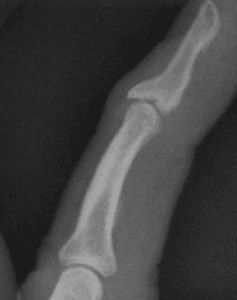

Fixation method for unstable bony mallet finger

A simple fixation method for unstable bony mallet finger A…